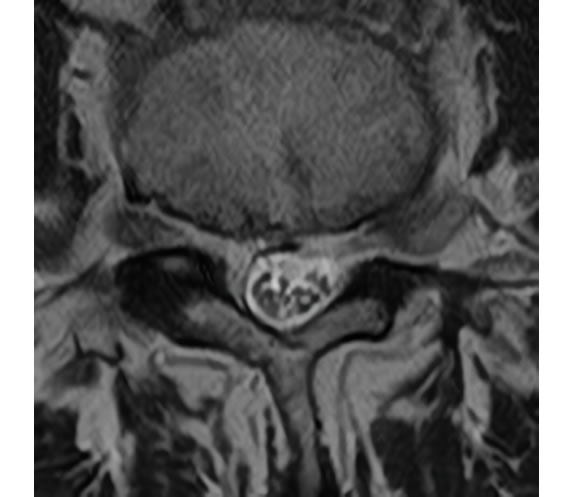

後方から内視鏡でアプローチする場合は椎弓の 間の 黄色靭帯、 および最低限の椎弓を切除して 、 内視鏡を進入させます。

(共に腰椎を輪切りした図)

ご高齢の方で、 骨の変形が強い場合は最低限の骨切除で椎間板、および靭帯を切除して、神経の圧迫を解除することもできます。

腰部脊柱管狭窄症術前

術後